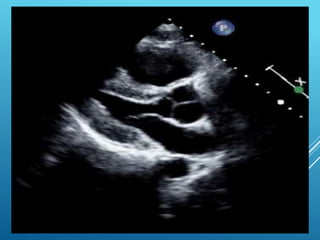

Q 32 37YEARS OLD MALE WITH ACUTE SOB AND PLEURITIC CHEST PAIN

Normal Size LV, Dilated RV

Q 32 ,THE DIAGNOSIS IS A- Dilated Cardiomyopathy B-Acute Sub Endo cardial ischemia C-Pulmonary embolism D-Acute STEMI

• 117.